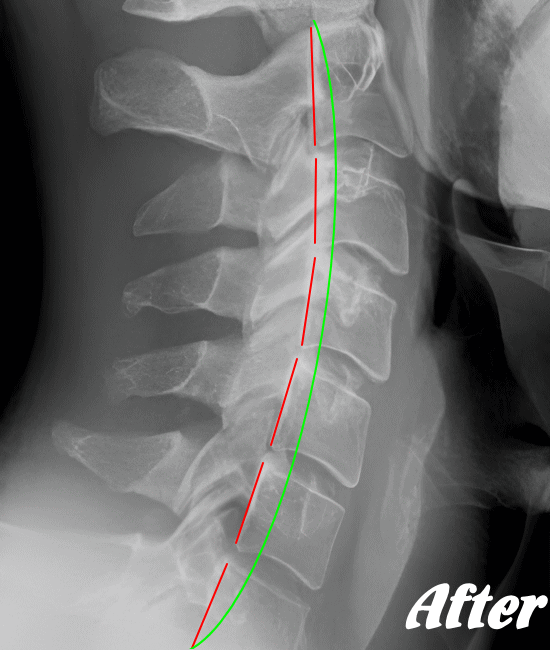

HALOカイロプラクティック☆平和島整体院では、骨盤(仙腸関節)から背骨(腰椎、胸椎、頸椎)、肋骨(肋椎関節)、肩甲骨(肩甲胸郭関節)などを調整し緩めることで、首(頚椎)にかかる負担を取り除き、可動域を良くして痛みを解消していきます。

首や肩周りの症状では、肩甲胸郭関節(肩甲骨周辺)を調整することは必須です。